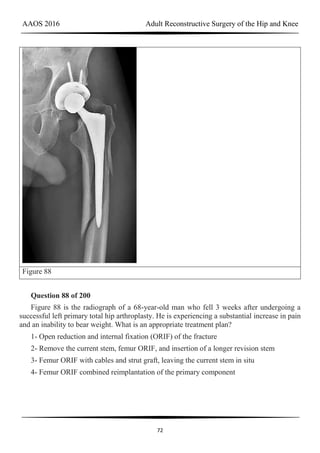

Question 148 of 200

During a revision total knee arthroplasty (TKA), there is difficulty gaining exposure and a

tibial tubercle osteotomy (TTO) is performed. The final components are stable and include a

stemmed tibial component that bypasses the osteotomy site. The tibial tubercle is reattached

to the osteotomy site with multiple cerclage wires. Following closure of the arthrotomy, the

knee is flexed to 90 degrees, and there is no observed displacement of the TTO. What is the